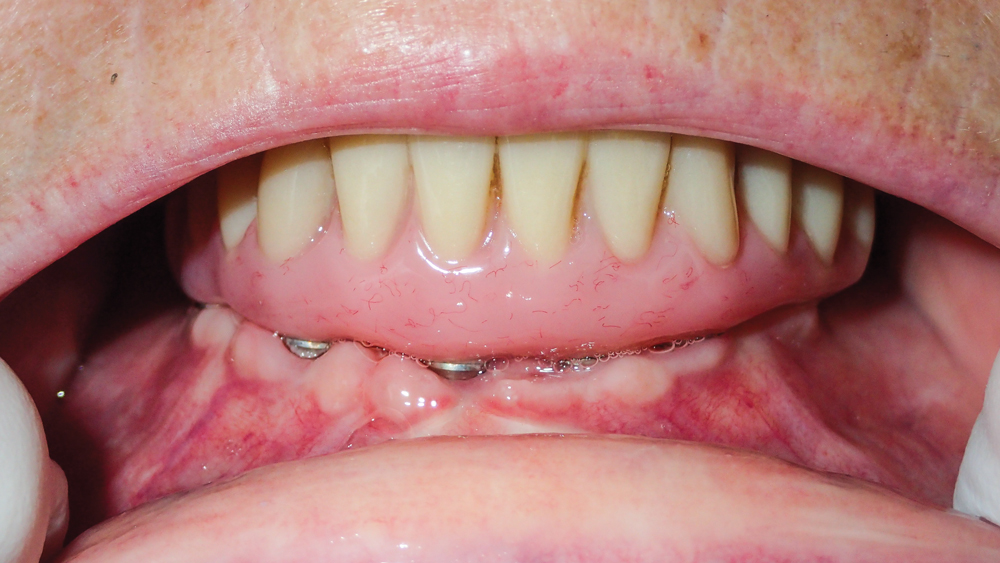

This patient was unhappy with the esthetics of her existing upper denture as well as the discomfort and instability caused by her loose-fitting mandibular partial denture. Although her concerns with the maxillary denture could be addressed with a new, more esthetic appliance, she preferred implant treatment for her mandible, where a fixed solution was needed to adequately restore function, stability and comfort.

The patient’s remaining mandibular teeth were extracted followed by immediate implant placement and delivery of a fixed provisional appliance. After integration of the implants, the prosthetic designs for the new upper denture and lower implant restoration were determined in tandem. Ultimately, the dual-arch restorations addressed the functional and esthetic challenges of the case while staying within the financial means of the patient, demonstrating the benefits of a flexible, multifaceted approach to restorative dentistry.

The dual-arch restorations addressed the functional and esthetic challenges of the case while staying within the financial means of the patient.